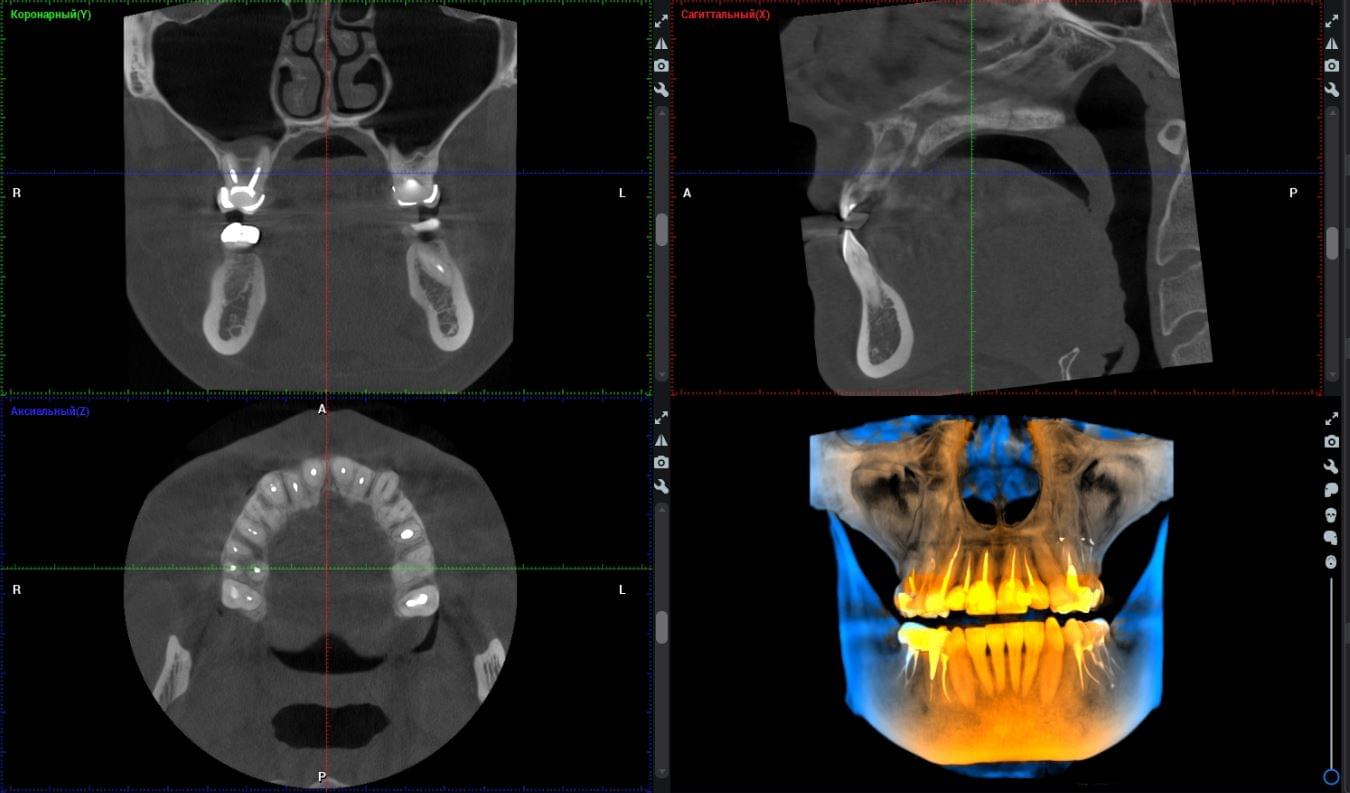

Коли коріння «ховає сюрпризи» - Корені зубів часто мають складну кривизну, гачкоподібні закручення або розгалуження, які на звичайному 2D-знімку накладаються один на одного, створюючи ілюзію прямого каналу. На плоскій картинці неможливо побачити реальний об'єм та напрямок вигину, що критично важливо при видаленні «зубів мудрості» або ендодонтичному лікуванні. КТ MyRay дає змогу лікарю заздалегідь побачити 3D-геометрію кожного кореня, оцінити його близькість до нижньощелепного нерва чи гайморової пазухи та підібрати правильну тактику роботи. Це мінімізує ризики поломки інструменту в каналі або травмування сусідніх структур, перетворюючи складну хірургію на прогнозовану процедуру.

При плануванні імплантації лікарю важливо знати дві речі: об'єм кістки та точне розташування нервів.

КТ дозволяє провести віртуальну операцію: встановити імплант у програмі, виключивши будь-які ризики травмування пацієнта.

Часто причиною зубного болю є гайморит, і навпаки — причиною запалення пазух є хворий зуб. На звичайному знімку пазуха виглядає як темна пляма. На КТ ми бачимо стан слизової, наявність кіст або сторонніх тіл (наприклад, залишків пломбувального матеріалу), що критично важливо для правильного діагнозу.